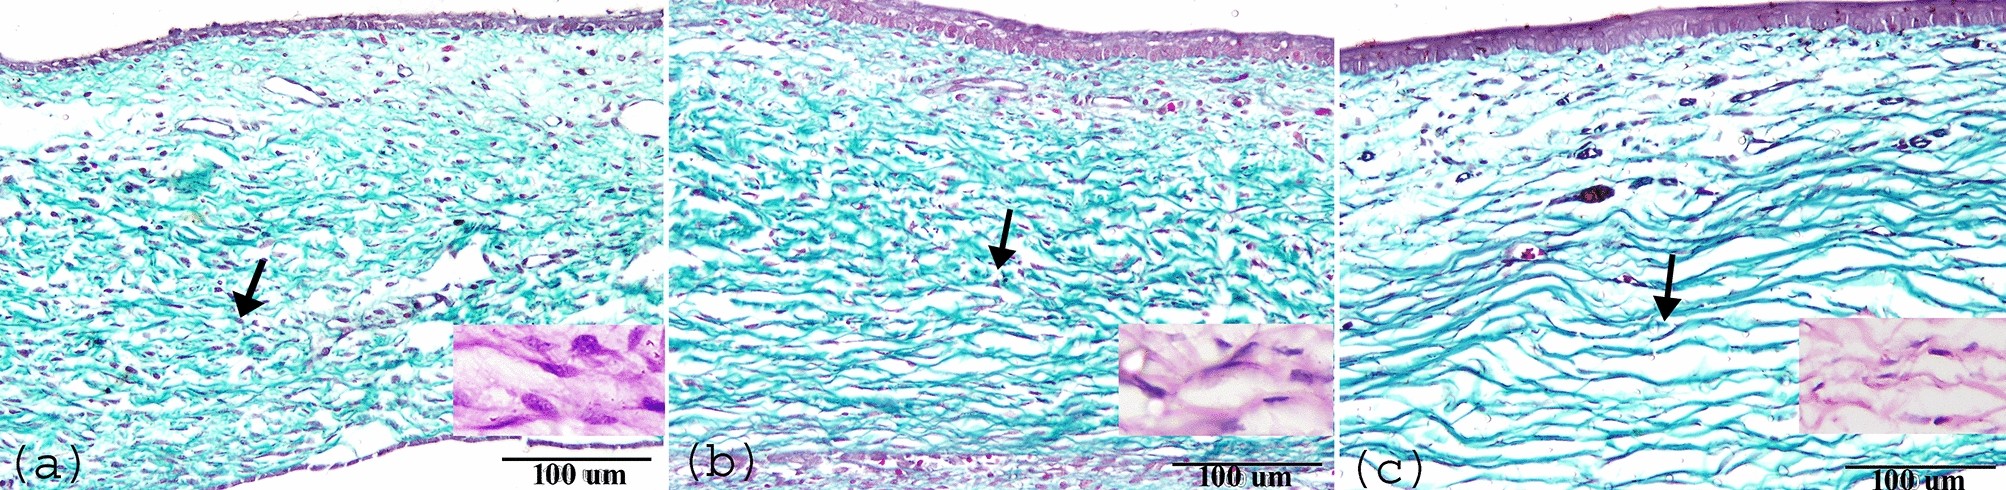

Figure 2

Paraffin sections showing postnatal development of limbal stroma stained with Crossmon's Trichrome (a) At PND7, (b) PND15, and (c) at PND30 showing the collagen fibers in the inner fibrous layer were more orderly organized with age (black arrow). Note the shape of the keratocytes nucleus transformed from oval to flat (H&E staining).